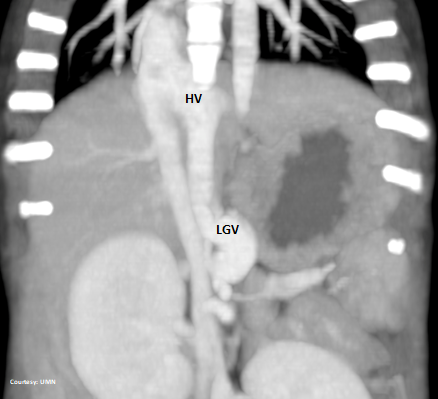

“LGHV +PancV -GSV”

Left Gastric – Left Hepatic Vein Shunt with Pancreatic Vein contribution and absent Gastrosplenic Vein